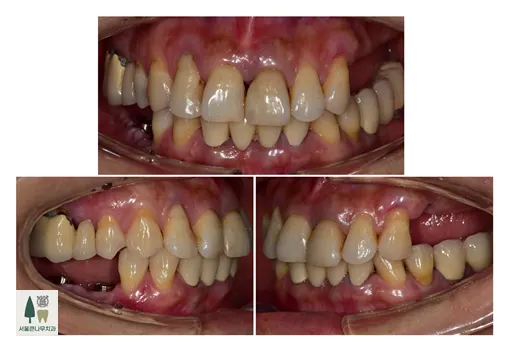

치료 전후 비교사진입니다

치료 전